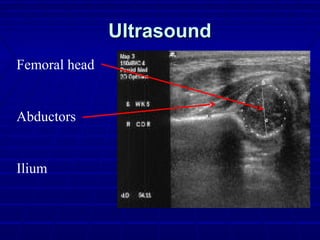

ImagingImaging

 UltrasoundUltrasound

 Introduced in 1978 for eval of DDHIntroduced in 1978 for eval of DDH

 Operator dependentOperator dependent

 Useful in confirming subluxation, identifyingUseful in confirming subluxation, identifying

dysplasia of cartilaginous acetabulum,dysplasia of cartilaginous acetabulum,

documenting reducibilitydocumenting reducibility

 Prox Femoral Ossification Center interferesProx Femoral Ossification Center interferes

 Requires a window in spica cast (avoid)Requires a window in spica cast (avoid)

UltrasoundUltrasound

Femoral head

Abductors

Ilium